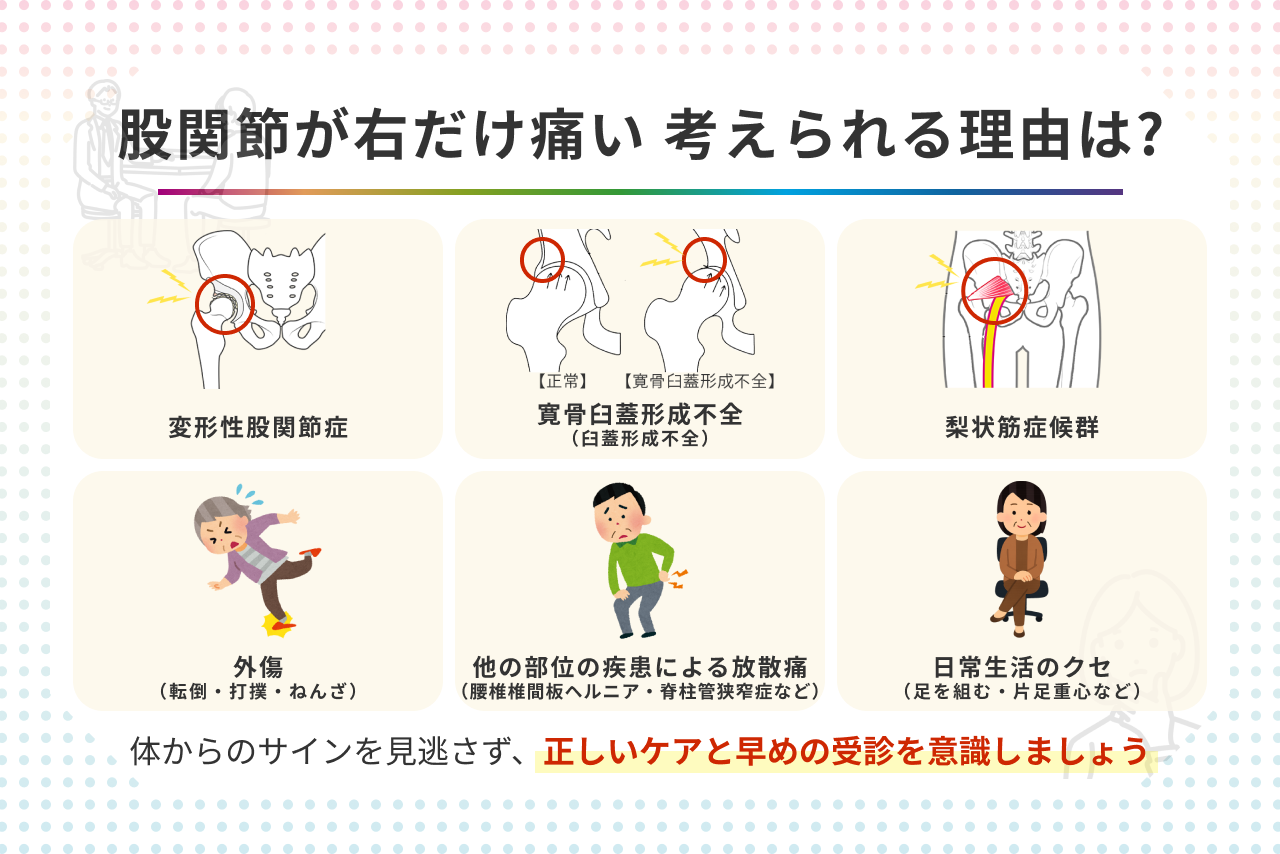

② 股関節 痛み 運動後に多い主な原因とは?

・筋肉・腱への負担(使いすぎ・オーバーユース)

「特にケガをした覚えはないのに、運動後から股関節が痛い」

こうしたケースで多いのが、筋肉や腱への負担の蓄積だと言われています。

ランニングやウォーキング、筋トレなどでは、股関節まわりの筋肉(お尻・太もも・内ももなど)が繰り返し使われます。普段より運動量が多かったり、急に強度を上げたりすると、筋肉や腱が疲労し、炎症のような反応が起こることがあるそうです。

・フォームや姿勢のクセによる影響

「同じ運動をしているのに、なぜか自分だけ痛くなる」

そんなときに考えられるのが、動き方や姿勢のクセです。

たとえば、

「反り腰気味で走っている」

「片脚に体重をかけるクセがある」

「股関節をあまり曲げずに脚だけで動いている」

こうしたフォームの乱れが、股関節に偏った負担をかけることがあると言われています。

本人は無意識でも、体の使い方によっては股関節だけが酷使され、運動後に痛みとして表れやすくなるようです。

「最近フォームを見直していないな…」という方は、一度振り返ってみるのも一つの視点かもしれません。